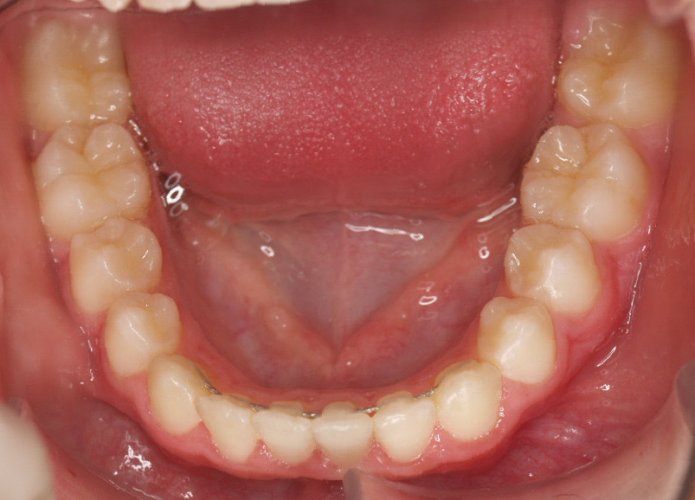

Un “diastema” es una separación extraordinariamente grande entre dos o más dientes. La mayoría de las veces, el diastema aparece entre los dos dientes delanteros superiores. Muchos niños tienen diastema cuando se les caen los dientes de leche, pero en la mayoría de los casos esta distancia desaparece cuando salen los dientes permanentes.

Los diastemas pueden deberse a una diferencia en los tamaños de los dientes, a la falta de algún diente o a que el frenillo labial sea demasiado grande. El frenillo labial es el tejido que va desde el interior del labio hasta la encía, en el lugar donde se sitúan los dos dientes delanteros superiores. Los diastemas también pueden deberse a problemas en la alineación de la boca, como la sobremordida horizontal o la protrusión de los dientes1.

- Realizar un tratamiento ortodóncico para mover los dientes y cerrar el diastema.